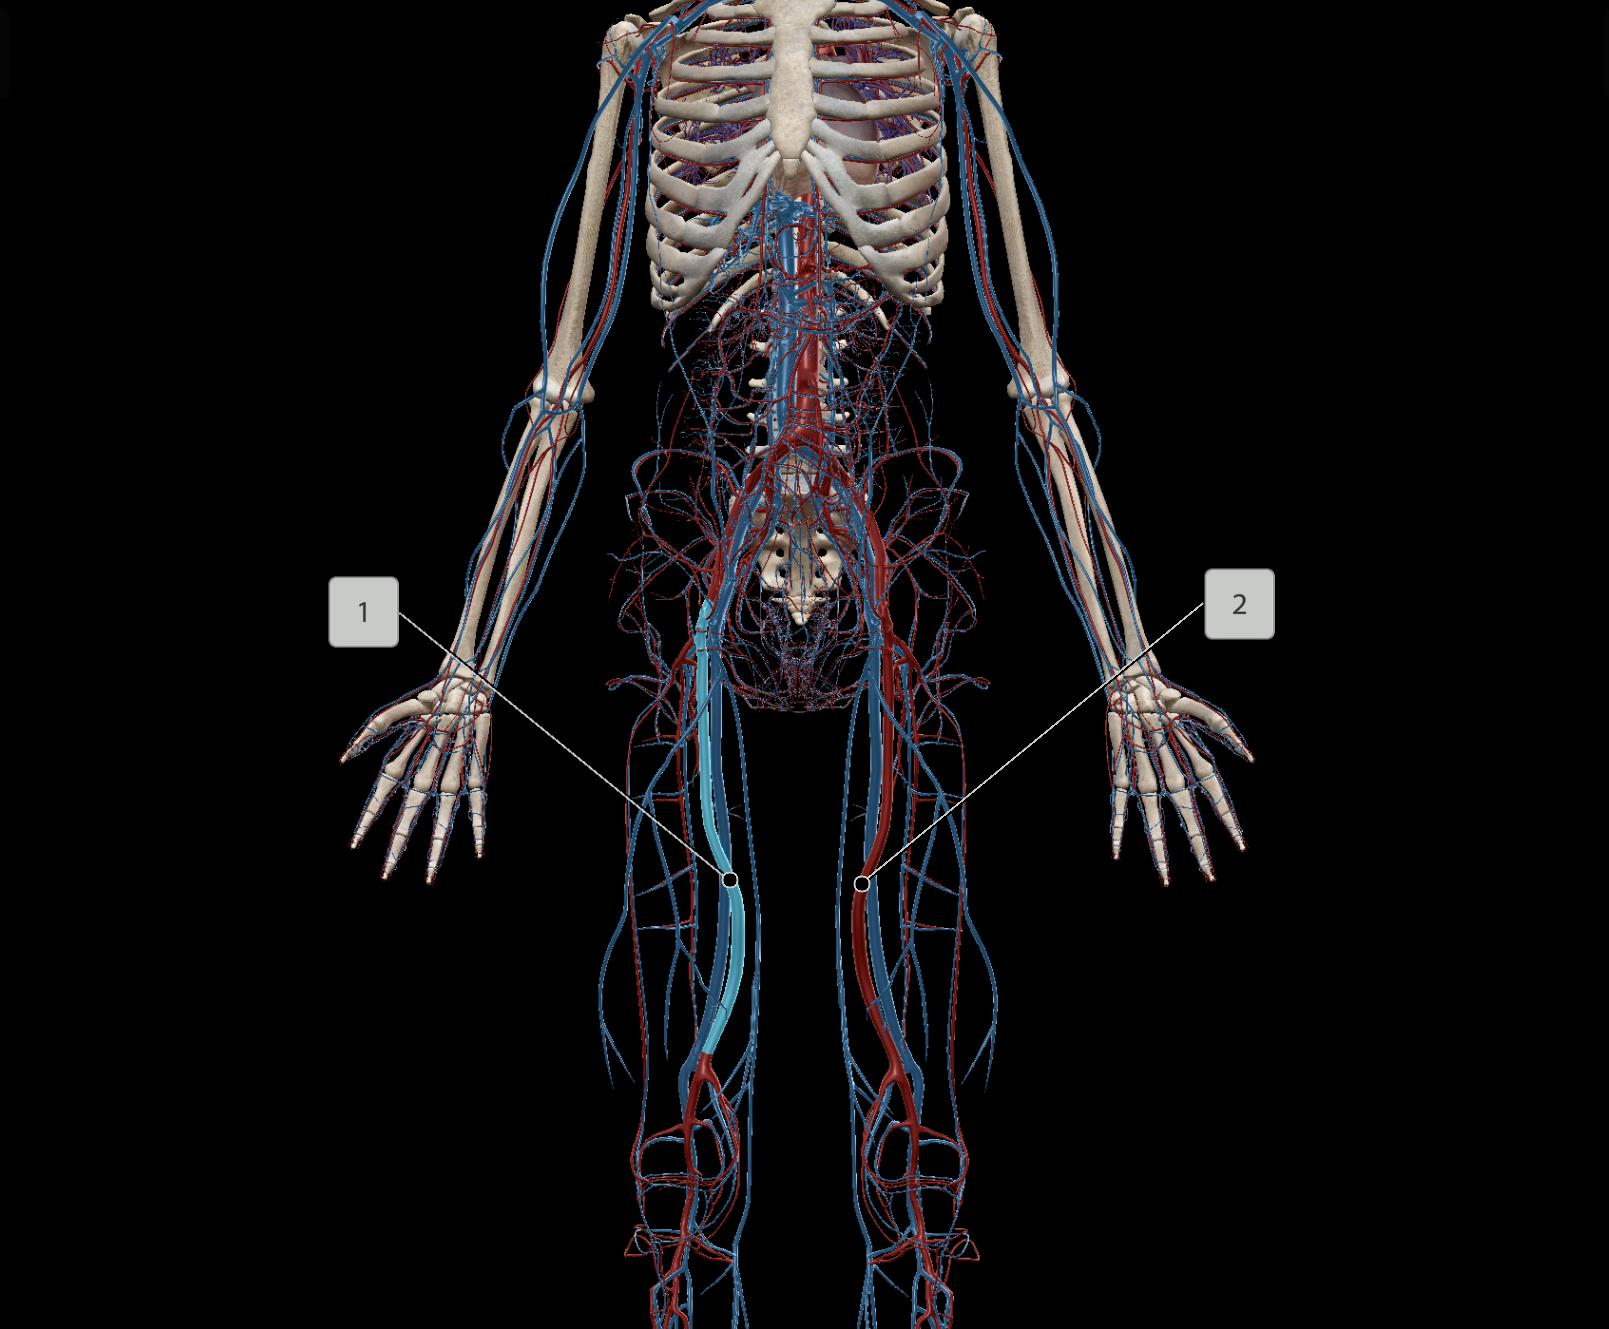

Inferior Vena Cava

External Iliac Artery

Femoral Vein

Common Iliac Vein

External Iliac Vein

Internal Iliac Vein

Popliteal Vein

Femoral Artery

Deep Femoral Artery